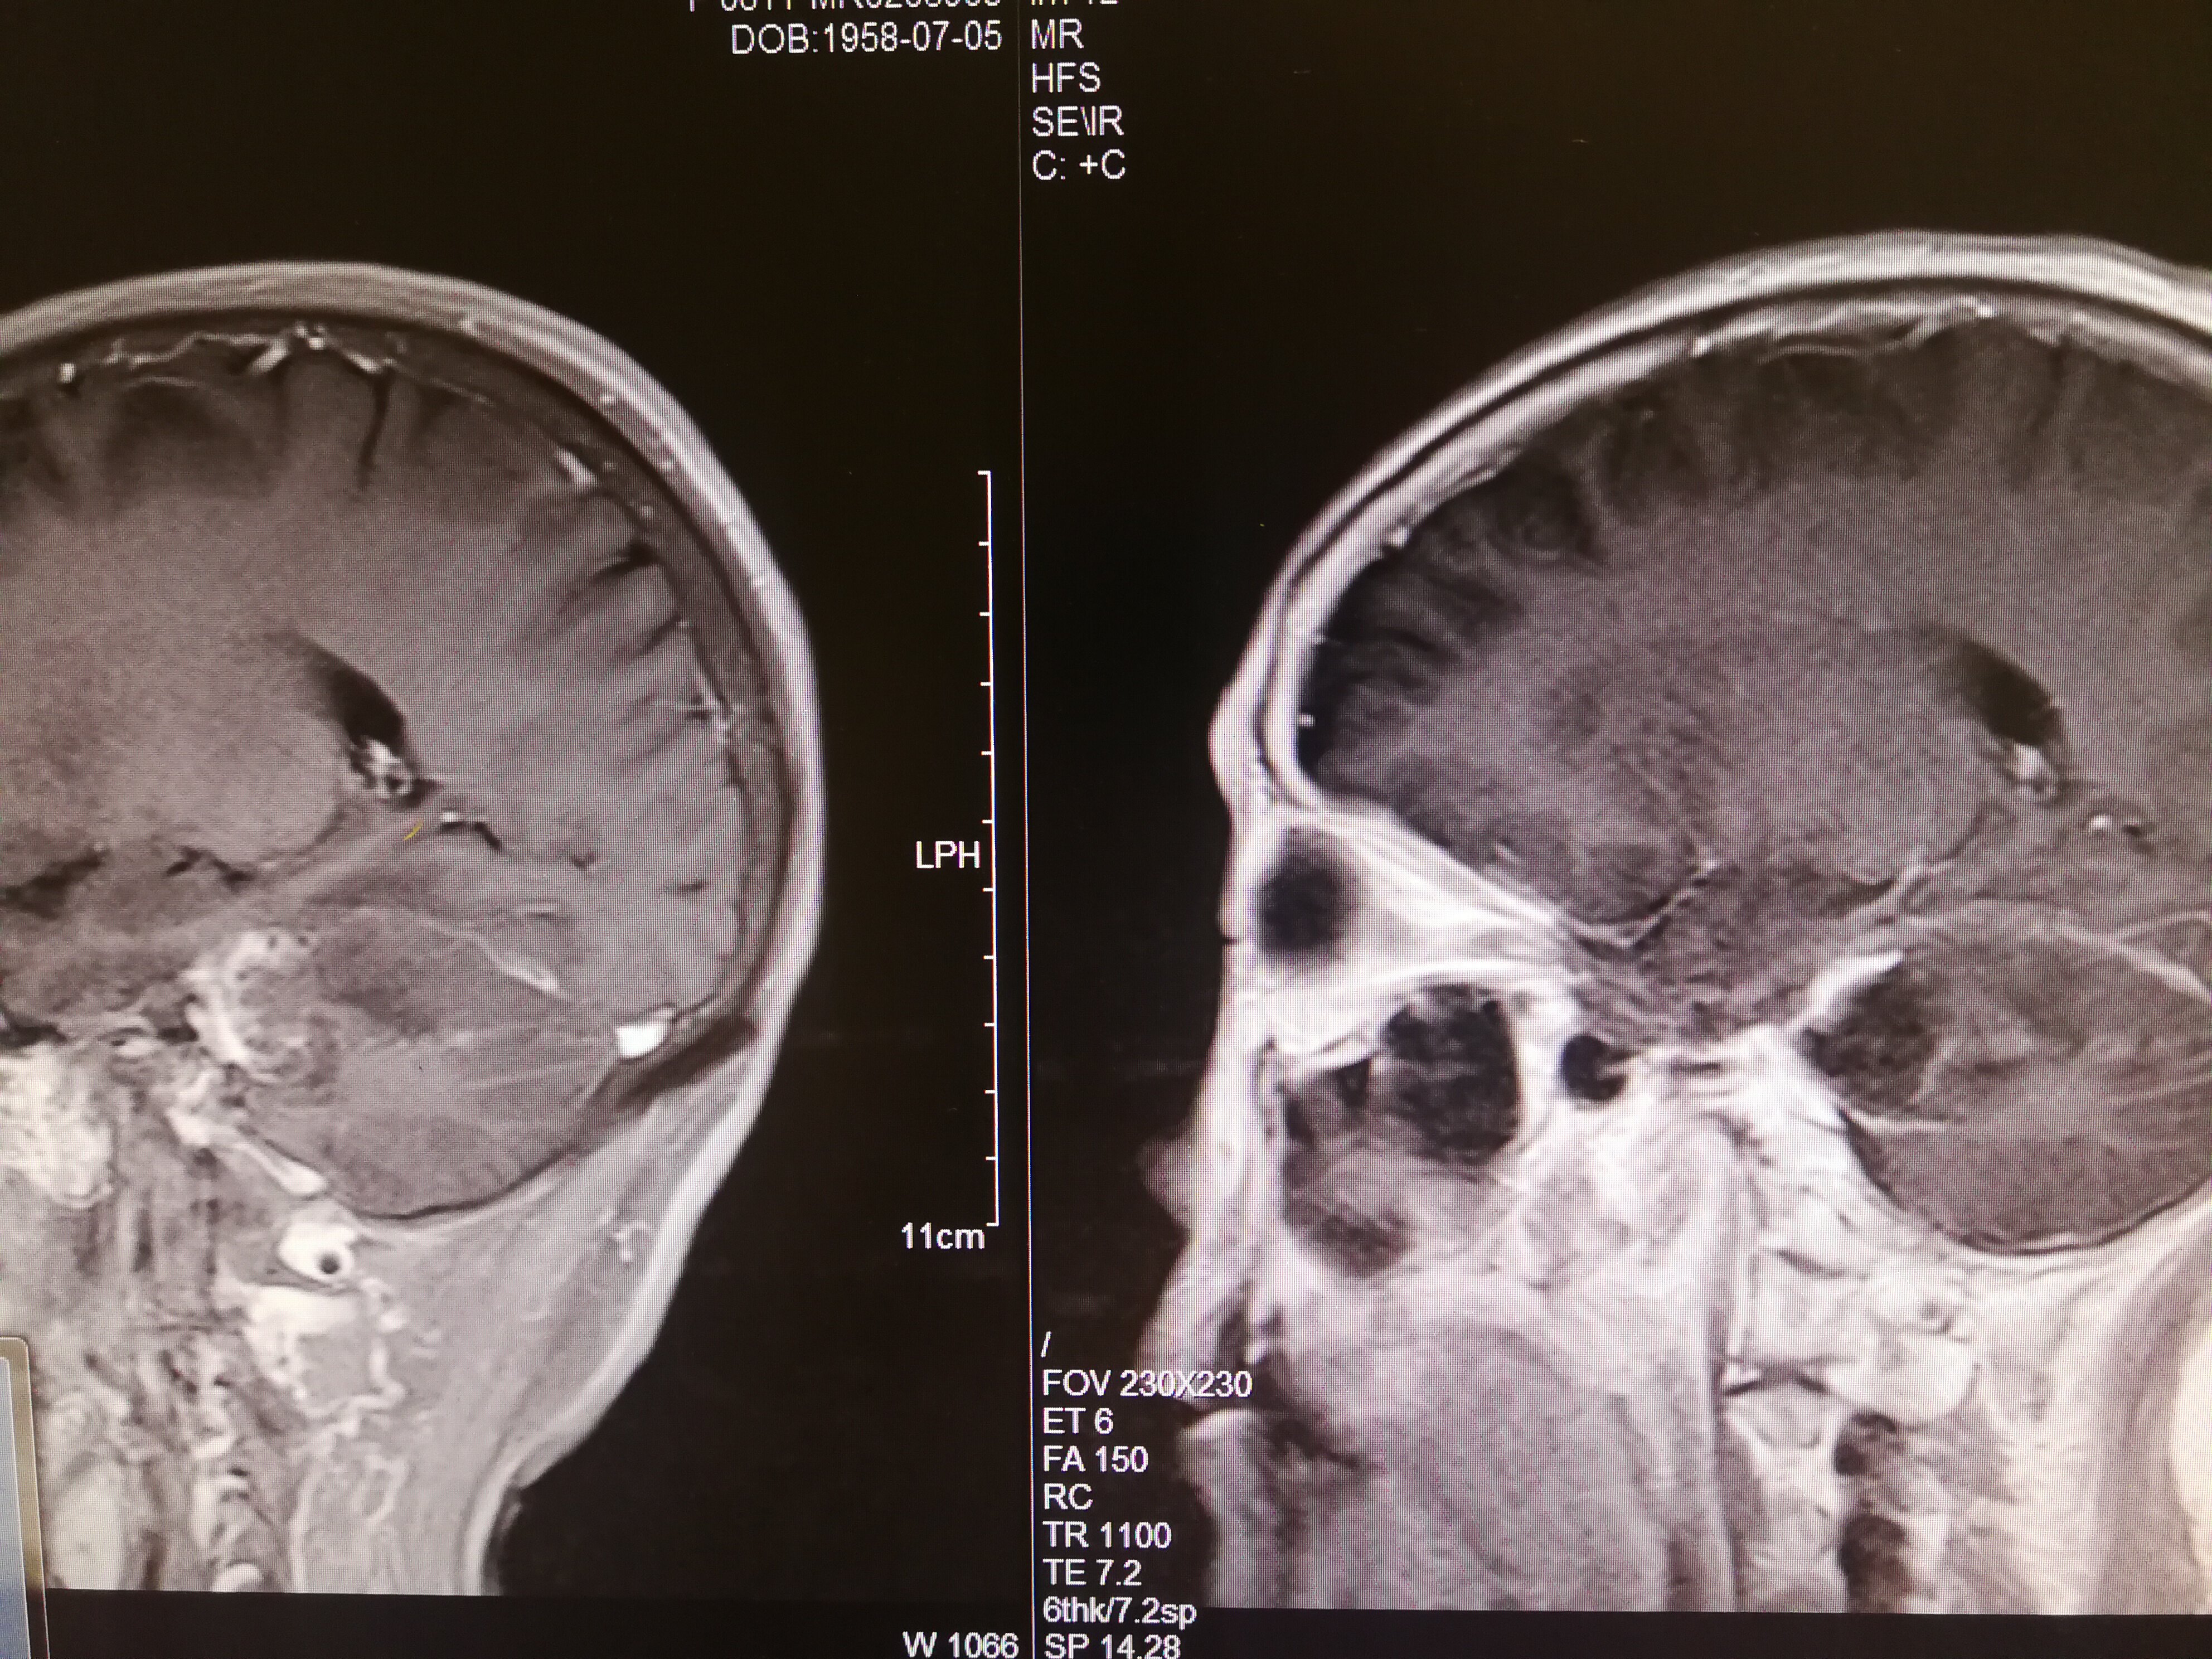

手术治疗听神经瘤是最主要的治疗方式,目前听神经瘤的手术已经非常成熟,只要没有明显的手术禁忌症首先应考虑手术治疗,并要求在电生理监测条件下完成手术,这样可以最大限度地保护面神经功能。以下是几例我们做的听神经鞘瘤手术前后核磁共振片子对照,除手术后听力不能恢复外,没有面瘫,脸部麻木,吞咽困难等颅神经症状,也无其他较明显的手术并发症发生。